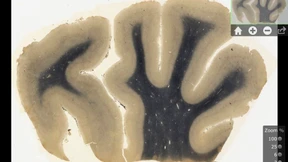

Auf 14 bisher unveröffentlichten Fotografien aus dem Jahre 1955 sieht man Einsteins frisch entnommenes Gehirn: Neuroanatomen haben die Bilder ausgewertet.

In den 50er Jahren stahl Dr. Thomas Harvey das Gehirn von Albert Einstein und zerlegte es in seine Einzelteile, um es für die Nachwelt zu erhalten. Das ist ihm gelungen: Bilder des Physiker-Hirns gibt es nun als App für das iPad.